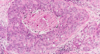

Q

A

TL: invasive ductal

TR: insitu ductal

BL: invasive lobu

BR: insitu lobular